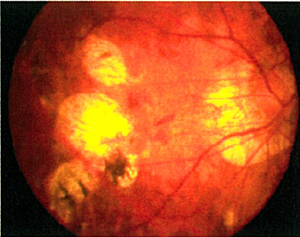

老年性(图4)及深近视性(图5)黄斑点退化的脉络膜新生血管膜之治疗

光动力疗法曾经是老年性及深近视性黄斑点退化的脉络膜新生血管膜的主要治疗,惟此治疗仅可维持已衰退的视力,或遏止视力进一步退化。现时,眼内药物注射(包括Lucentis丶Avastin丶Eylea及类固醇)是常见治疗方法,能让大部份病人回复一定程度的受损视力。而且注射过程安全,甚少出现副作用。

![]() 图4:老年性黄斑点退化-出血 |